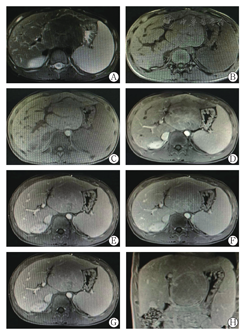

男性患者,15岁,因"间断上腹部不适,发现腹部包块1年余"于2016年4月11日入院。患者1年余前无明显诱因间断出现上腹部不适,每月3~4次,每次持续几小时或几天不等,无明显规律,与进食无关,于剑突下可触及一质软包块,无压痛,未诊治,4天前为明确诊断来我院门诊,行腹部强化磁共振检查显示:肝左外叶局限性增大,符合增生性病变MR表现,脾大,双肾多发囊肿,见图1。今为求进一步诊治来我院,门诊以"肝脏占位"收入我院肝胆外科,患者自发病以来,饮食、睡眠、大小便无特殊,体质量无明显变化。既往史、个人史均无特殊。家族史:其母亲腹部CT:肝脏多发囊肿,双肾多发囊肿,点状血肿可考虑。体格检查:查体未见明显异常,移动性浊音(-),Murphy征(-),肠鸣音3~4次/min。入院后查血常规尿常规、大便常规正常;肝功能指标:丙氨酸氨基转移酶66 U/L,天冬氨酸氨基转移酶53 U/L,γ-谷氨酰转移酶为56 U/L;碱性磷酸酶384 U/L,白蛋白41.6 g/L,总胆红素7.70 μmol/L;凝血酶原时间13.1 s;甲胎蛋白4.64 ng/ml;降钙素原0.4 ng/ml;C反应蛋白0.02 mg/L;抗平滑肌抗体1∶100(+),抗核抗体、抗线粒体抗体、抗双链DNA等免疫指标均(-);免疫球蛋白未见异常。病毒学检测指标:HBsAg(-);丙型肝炎抗体(-),人类免疫缺陷病毒抗体(-),梅毒抗体(-),EB病毒DNA(-),巨细胞病毒DNA(-);血清铁蛋白、血清铜、铜蓝蛋白、甲状腺功能、心肌酶谱未见异常;尿常规、大便常规均未见异常;心电图、心脏超声未见明显异常;胸片、肺功能正常。

注:肝左外叶见团块状长T1异常信号灶,大小约9.3 cm×6.1 cm×8.6 cm,邻近组织受压移位,注入GD-DTPA后病变与肝实质强化程度相似,其内可见血管走行,胰腺形态及信号未见明显异常,胆囊不大,肝内胆管未见明显扩张,双肾内见多发囊状长T2无强化灶,最大者位于右肾上极,直径2.1 cm,脾大,厚5.1 cm,信号未见明显异常。影像学诊断:(1)肝左外叶局限性增大,符合增生性病变MR表现;(2)脾大;(3)双肾多发囊肿